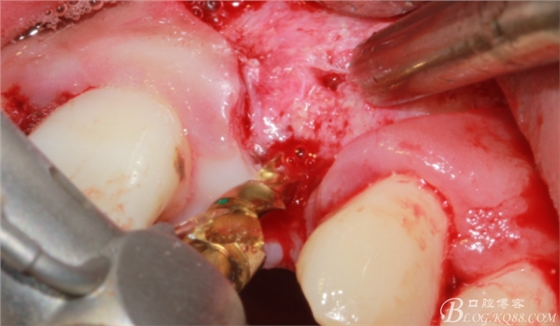

再次翻瓣。

先行粘骨膜減張,取自體血液。

根方用取骨鉆取自體骨。

旋入一長(zhǎng)兩短3顆鈦釘。

將自體骨與BIO-OOS骨粉混合植到術(shù)區(qū),蓋生物膜。